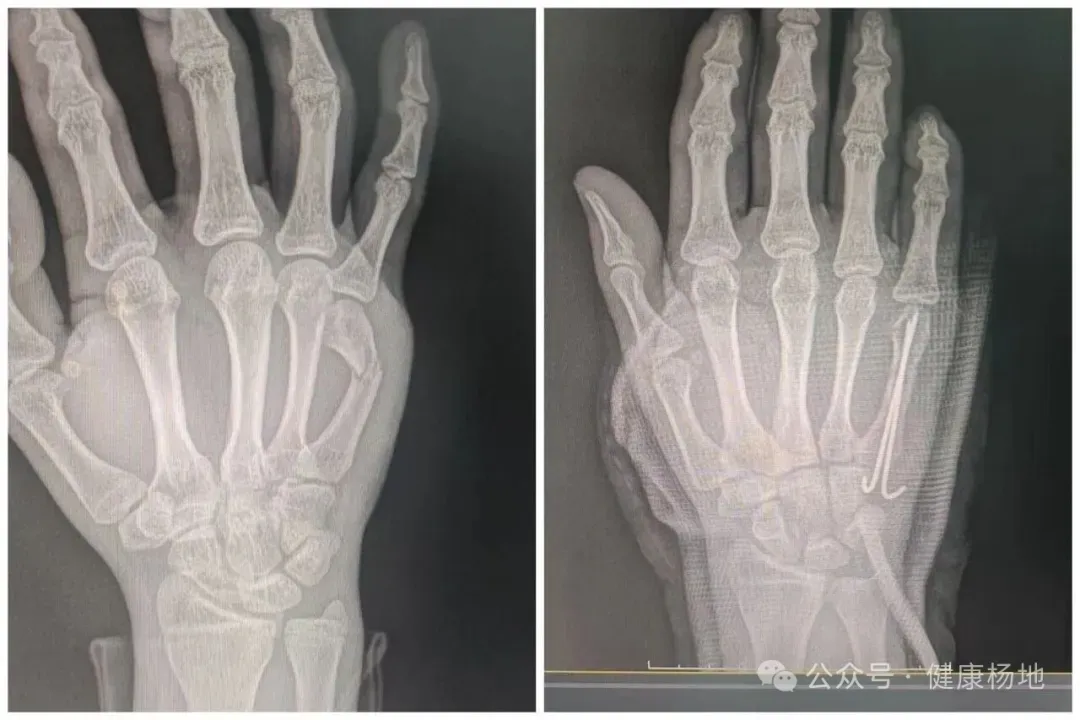

不久前,一位患者因右手不适就诊,梁磊医生细致检查后确诊其右手第5掌骨远段骨折。考虑到基层医疗条件限制,为保障治疗精准度,卫生院建议患者转往上级医院。可意外接踵而至——患者从上级医院返回后,骨折处的内固定突然脱落,伤口还引发皮肤感染,剧烈疼痛让他坐立难安,生活陷入困境。

焦急万分的患者和家属,第一时间想到了梁磊医生。再次来到卫生院时,梁磊医生见状毫不犹豫,立刻展开全面检查。深知情况紧急的他,迅速制定治疗方案,紧急为患者实施内固定植入术,同时清理感染伤口、涂抹药物,并开具消炎止痛药品。手术中,他专注细致、动作轻柔,凭借扎实的医术顺利完成操作;术后更是时刻关注恢复情况,耐心叮嘱护理要点,用细致关怀缓解患者的痛苦与焦虑。